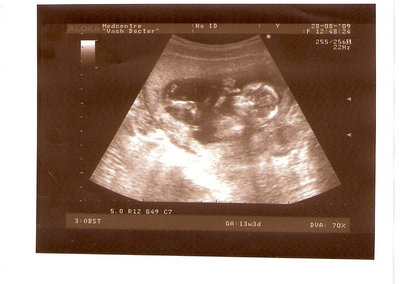

СЫН

| Вложения: |

2.jpg [ 110.14 КБ | Просмотров: 2448 ]

Nikisa писал(а): Foto prosto chudesnoe. A na kakom sroke uznali, chto sin.............. НА 13 НЕДЕЛЯХ.КАК РАЗ ВОТ В ЭТО узи, ОНО УМЕНЯ ВТОРОЕ БЫЛО. ЭТО КОНЕЧНО МАЛЕНЬКИЙ СРОК ДЛЯ ОПРЕДЕЛЕНИЯ ПОЛА. НО Я ПОПРОСИЛА ВРАЧА(ЭТО КТСТАТИВ РОССИИ БЫЛО) ХОТЯ БЫ ПРЕДПОЛОЖИТЬ. ЕЙ ВСЁ ТАКИ УДАЛОСЬ РАССМОТРЕТЬ.НУ ВООБЩЕМ ЧЕРЕЗ НЕСКОЛЬ ДНЕЙ ПОЙДУ К ВРАЧУ, УЖЕ АМЕРЕКАНСКОМУ И УЗНАЮ ТОЧНО. К ТОМУ ВРЕМЕНИ У МЕНЯ БУДЕТ СРОК 18 НЕДЕЛЬ. ХОТЕЛОСЬ БЫ ПОСМОТРЕТЬ НА ДРУГИЕ ФОТО НА ЭТОМ СРОКЕ ИЛИ БОЛЬШЕ. ТАК ЧТО ВЫКЛАДЫВАЙТЕ, ЕСЛИ НЕ ЖАЛКО!